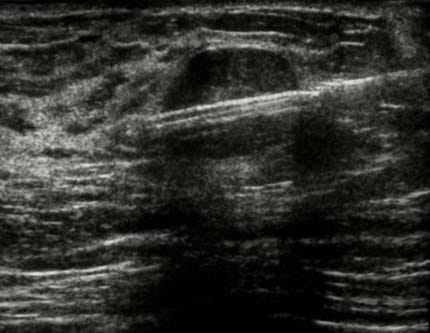

Sous Guidage Échographique : Prélèvement de cellules d'un nodule thyroïdien à l'aide d'une aiguille fine pour une analyse cytologique, déterminant la nature bénigne ou maligne du nodule.

Le geste est effectué sous contrôle visuel continu (Écho ou Scanner) pour une précision maximale.